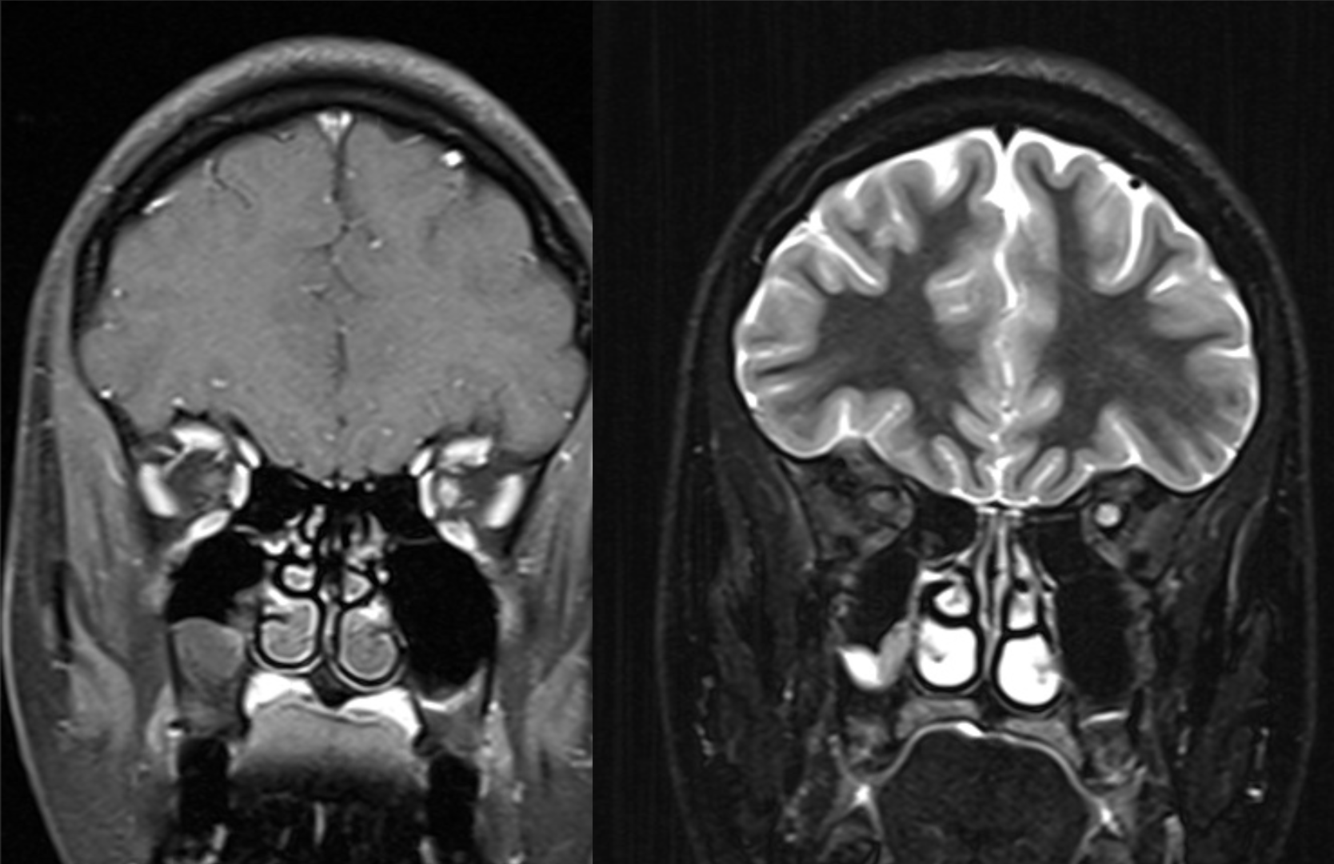

A 24 year-old man presented with left arm weakness.

Multiple sclerosis - Balos